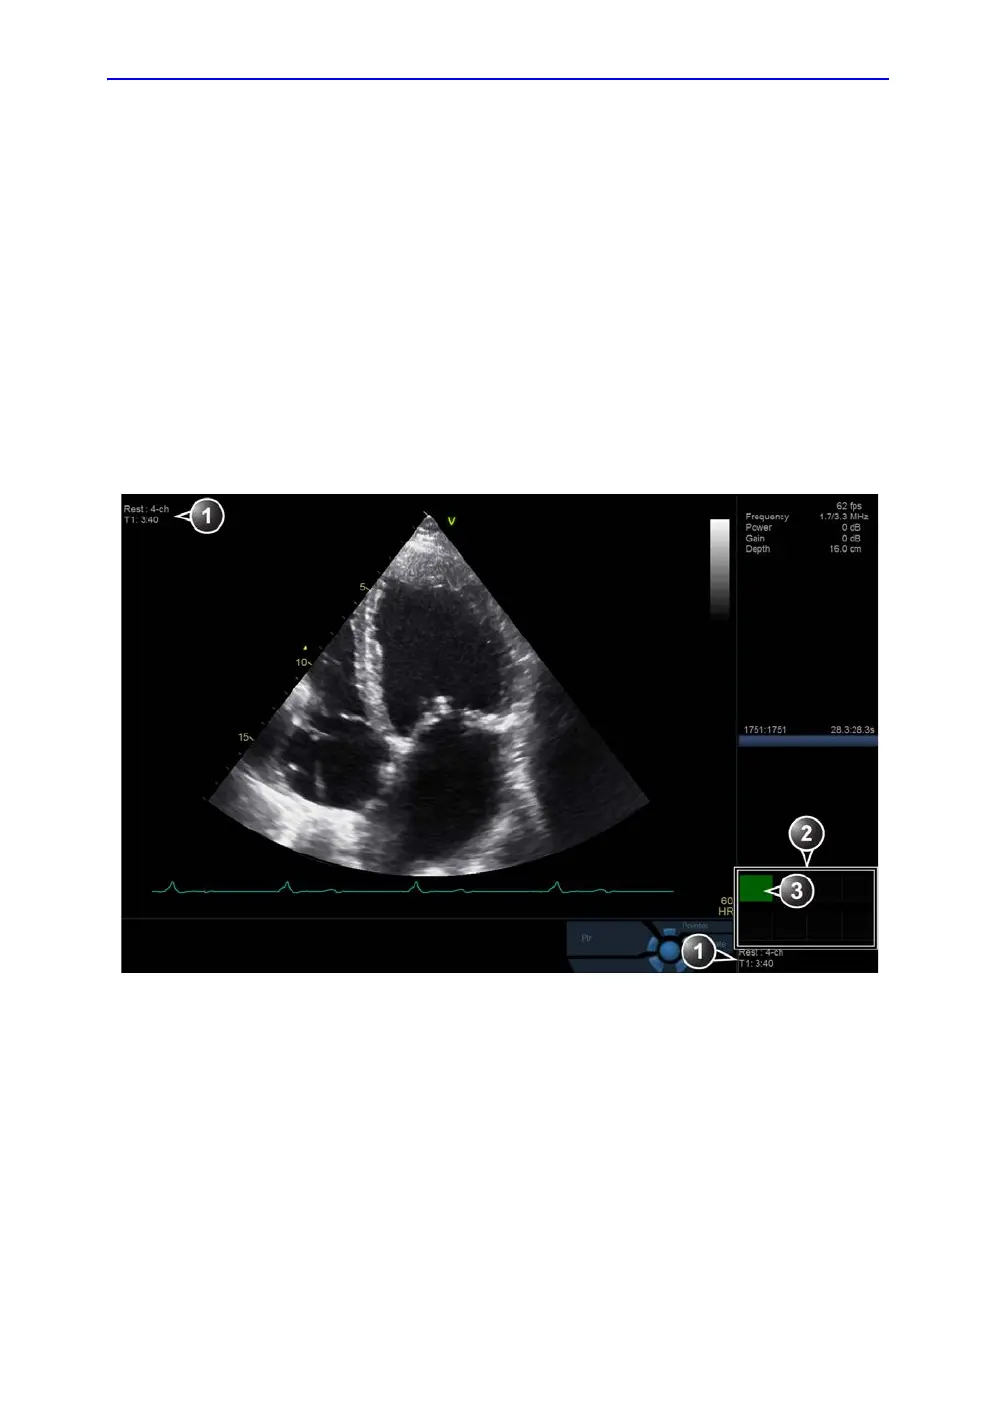

Images are acquired in a pre-defined order, according to the

selected template. The highlighted cell (green) of the matrix,

displayed in the Clipboard window indicates which view is

currently being acquired (see Figure 7-2). The names of both

the view and the level for the current cell is displayed on the top

corner of the image area and under the template matrix.

Figure 7-2. The stress mode acquisition screen

1. Current view, level and timers

2. Template matrix view and level

3. Current view (Green cell)